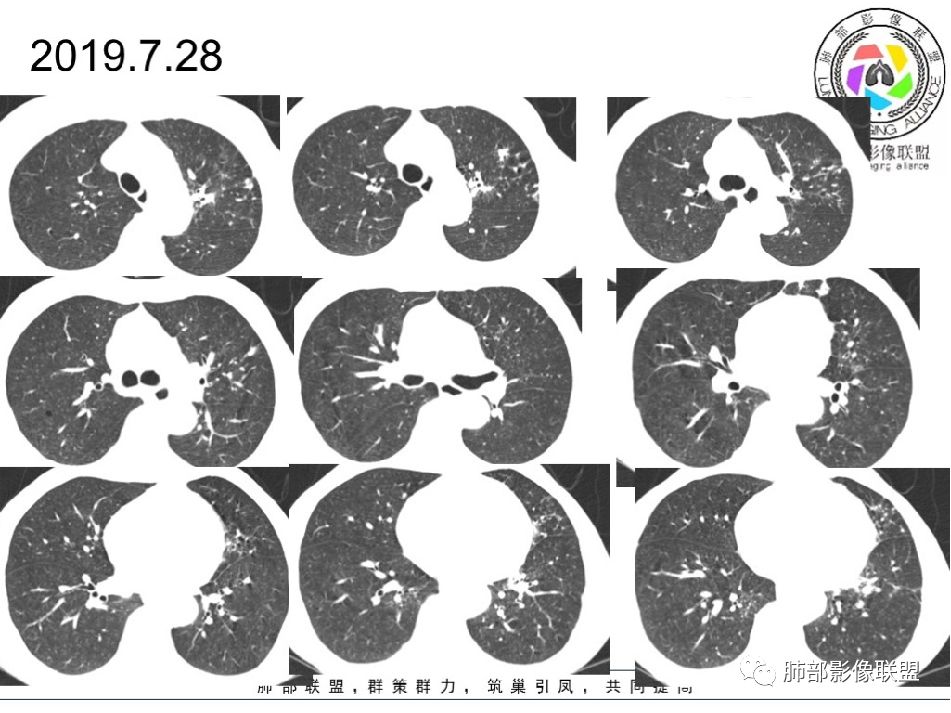

2019-7-28CT左肺病变较前进展(下肺为著,多为新发),左上肺空洞较前增大;

第二次住院(8.1-8.27):哌拉西林他唑巴坦抗感染10天复查,左肺病变进展,左上肺空洞缩小;改为DL2EMFX抗结核护肝;IgM(-),免疫球蛋白E1090.0IU/ml,病情好转出院。

思维过程:2019-10-8小空洞,2019-7-28是不是也有?二元论解释,结核,有效;但又新发有新病灶,空洞前期变大;上腹部隐痛,手指关节间断痛,IgE是不是明显增高,有意义?